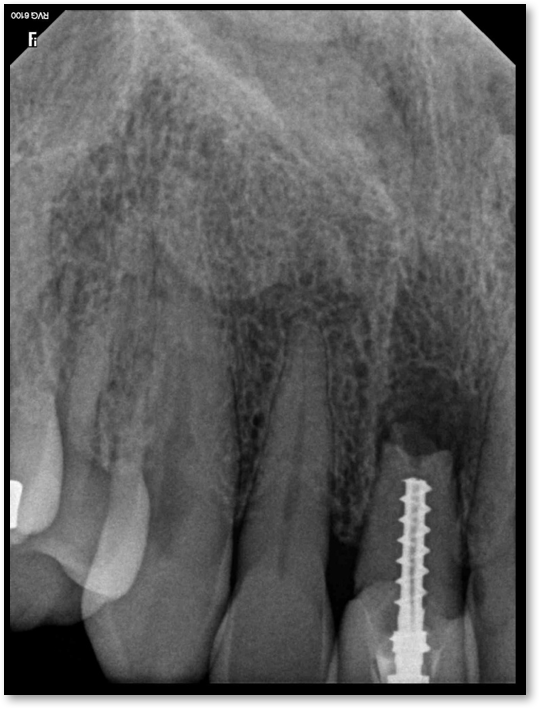

If a tooth stands alone, greater forces will be placed on it because it has no adjacent teeth to provide support. This situation will affect the decision-making process for placing a post. Figure 3 shows a tooth that was on an island and would be having three implants placed in front of it. The tooth would take a much greater beating than another tooth that had support proximally. Even though it had a good root canal, the clinician would need to account for whether the tooth would last until the implants integrated. Figure 4 shows a case that would quickly proceed to implants. The patient had a less-than-ideal bridge for over a decade, with decent endodontics and functionality. There was also an overhang on the premolar. The post was not ideal in this case because there was one distal canal and not all the gutta-percha was removed from it. An intimate fit should be the goal with the post and the walls. Whether using a threaded or non-threaded post, there should not be excess gutta-percha because it is not as solid as the tooth and will lead to greater movement. That movement on the tooth and bridge will create too much force and result in demise.

Fig 4. Case that quickly would proceed to implants.

Figure 4